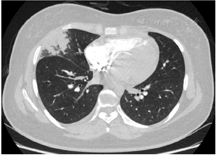

入院查血常规示白细胞计数为10.0×109/L,中性粒细胞比例为59.7%,血红蛋白为93 g/L,血小板计数为479×109/L,平均红细胞体积为71.9 fl,平均红细胞血红蛋白含量23.0 pg,平均红细胞血红蛋白浓度321.0 g/L。尿便常规、肝肾功能、电解质、心肌损伤标志物均正常。超敏C反应蛋白为78.52 mg/L。同型半胱氨酸为10.30 μmol/L。D二聚体为2.32 mg/L。红细胞沉降率为106 mm/h。降钙素原、血尿免疫固定电泳均阴性。直接抗人球蛋白试验弱阳性。抗核抗体阳性(颗粒型1:100),抗ENA谱阴性。免疫球蛋白A 4.5↑ g/L,补体C4 0.376↑ g/L,免疫球蛋白M、免疫球蛋白G和补体C3均正常。类风湿因子、抗环瓜氨酸肽抗体、抗中性粒细胞胞浆抗体、抗肾小球基底膜抗体、狼疮抗凝物、抗心磷脂抗体、抗β2-糖蛋白1抗体均阴性。抗凝血酶活性、蛋白C、蛋白S活性均正常。双下肢深静脉超声未见血栓。超声心动图示左心室射血分数正常,主动脉瓣中度反流,右心室收缩功能正常,肺动脉收缩压正常。肺动脉CT提示右肺上叶前段及右肺中叶肺动脉闭塞,右肺动脉干远端及左肺下叶前基底段肺动脉管腔变窄(图1);右肺中叶远端胸膜下楔形实变灶,尖端指向肺门、周围可见片状磨玻璃影、内可见充气支气管气相(图2);右肺上叶前段胸膜下可见小片状实变灶伴磨玻璃密度;肺实质病变分布位置符合右肺上叶前段、右肺中叶肺动脉供血区域;升主动脉管壁可疑增厚。正电子发射计算机断层显像(positron emission tomography, PET-CT)示升主动脉管壁环形葡萄糖代谢增高,管壁稍增厚、毛糙(图3),考虑大动脉炎可能大。